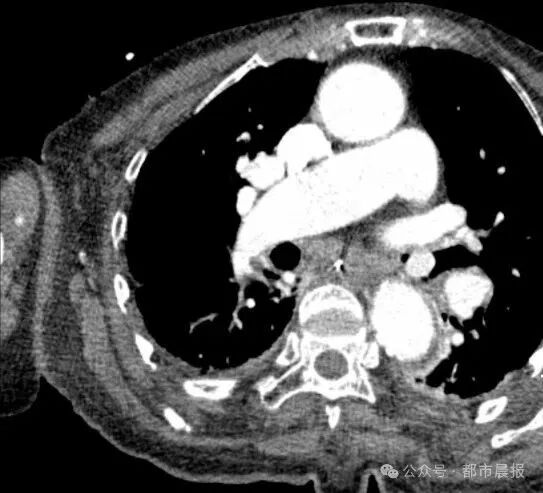

68岁的徐先生(化名)此前因慢性肺病反复住院,半月前刚病情稳定出院。然而两天前突现剧烈胸闷、喉部喘鸣,CT检查发现右侧主气管卡着一颗直径约1.5厘米的类圆形异物。

追问得知,患者发病前曾边谈笑边吃枇杷,虽经剧烈咳嗽仍误将果核吞入气道。呼吸科主任柳志浩介绍:“这颗果核随呼吸上下移动,随时可能完全阻塞气道引发窒息,必须立即镜下取出。”

医生透露,枇杷核表面光滑的特性给救治带来特殊挑战。常规异物钳难以夹取,需采用圈套器配合网兜技术,且在全身麻醉下精细操作。